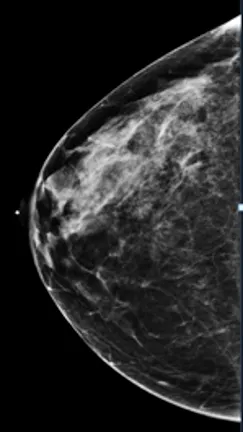

A standard 2D digital mammogram is a common method, and some facilities in the United States perform only these screenings. Digital mammograms are superior to film-screen mammograms, which are being phased out. Now, 3D breast imaging, or tomosynthesis, is a common method.

Current scientific literature suggests that this is superior to the traditional 2D mammograms, which has some disadvantages.

Normal breast tissue may mimic an abnormality due to overlap, resulting in a false positive test and a call back for additional testing.

A small cancer is masked by the normal breast tissue resulting in a false negative interpretation.

In 3D tomosynthesis, thin slices of the breast are obtained, and evaluation of the breasts is like flipping the pages of a book. This makes the examination more sensitive, improving the ability to detect invasive cancers by 15 to 22%, and reduces the likelihood of false positive and false negative results.

Compare these two images. You can see the benefits of 3D tomosynthesis. A small cancer (circled) on tomosynthesis slices in image A (left) is not apparent in the standard 2D mammogram, image B (right) of the same patient and same projection.